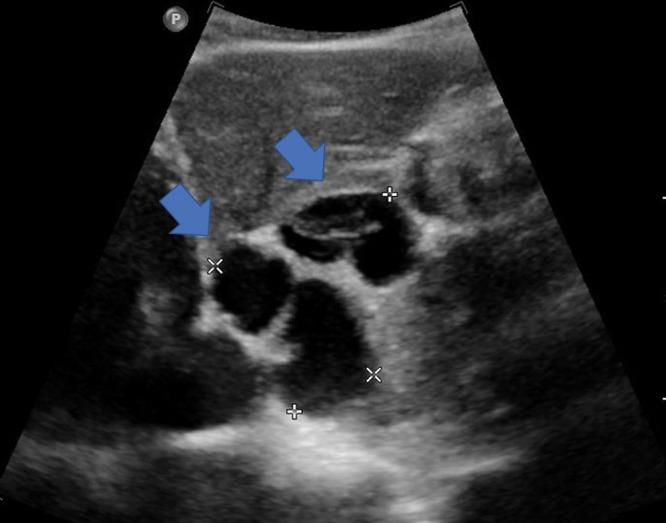

胆管黏液性囊腺瘤:文献综述

Biliary Mucinous Cystadenoma: A Review of the Literature.

Biliary mucinous cystadenomas are cystic neoplasms commonly mistaken for simple cysts. They are rare and generally benign tumors, often incidentally found on imaging and during unrelated surgical interventions. They tend to be slow growing though may reach symptomatic dimensions. Misdiagnosis of biliary mucinous cystadenomas may have serious consequences secondary to their potential for malignant transformation into biliary mucinous cystadenocarcinomas. Here, we review the epidemiology, etiology, pathology, diagnostic modalities, histology, and available treatment methods for mucinous cystadenomas reported in current literature.

摘要

胆管黏液性囊腺瘤是一种囊性肿瘤,常被误诊为单纯囊肿。它们是罕见的肿瘤,通常为良性,常在影像学检查或无关手术中偶然发现。虽然生长缓慢,但可能会发展到出现症状的大小。胆管黏液性囊腺瘤的误诊可能会导致严重后果,因为它们有可能恶变为胆管黏液性囊腺癌。在此,我们综述了当前文献中报道的黏液性囊腺瘤的流行病学、病因、病理、诊断方法、组织学及可用的治疗方法。